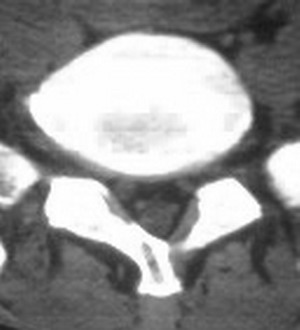

以下是引用fumaogui在2007-4-7 10:58:00的发言:[br]右侧腰4-5及骶1水平右侧神经根较对侧增粗,建议做mri排除一下神经源性肿瘤.

以下是引用zjzjr在2007-4-7 11:00:00的发言:[br]考虑腰4--5椎间盘突出长期压迫刺激致腰5神经根水肿,建议mr除外占位性病变。